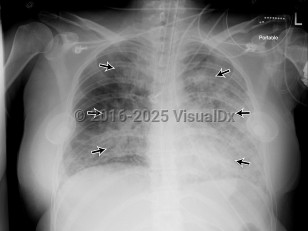

Chest pain, Dyspnea, 50-59 year old Female

Acute respiratory distress syndromeAcute respiratory distress syndrome